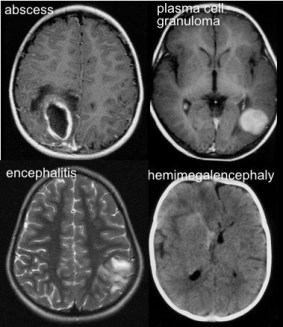

- de s’assurer qu’il s’agit bien d’une tumeur (cf. diagnostics différentiels ci-contre)